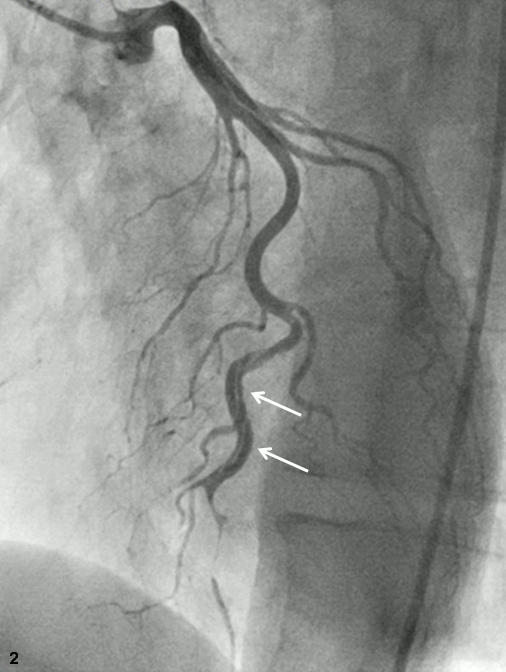

Abstract PDF ECG 1 Angio 1 Angio 2 Angio 3 Angio 4 ECG 2 Table Chart Original File 1 2 3 4 5 6 Reply to reviewer Fig. 1. ECG during myocardial infarction Fig. 2. Coronary angiography of LCA during myocardial infarction Fig. 3. Coronary angiography of LCA during myocardial infarction Fig. 3a. Coronary angiography of LCA during myocardial infarction Fig. 4. Coronary angiography of LCA 2 years after myocardial infarction Fig. 5. Coronary angiography of LCA 2 years after myocardial infarction Fig. 6. ECG 2 years after myocardial infarction Fig. 7. Thrombolytic trials in patients with coronary artery dissection Fig. 8. Flow chart of the study selection process -

Successful primary percutaneous coronary interventions in a patient with two consecutive ST-segment elevation myocardial infarctions and dual left anterior descending artery (type IV)